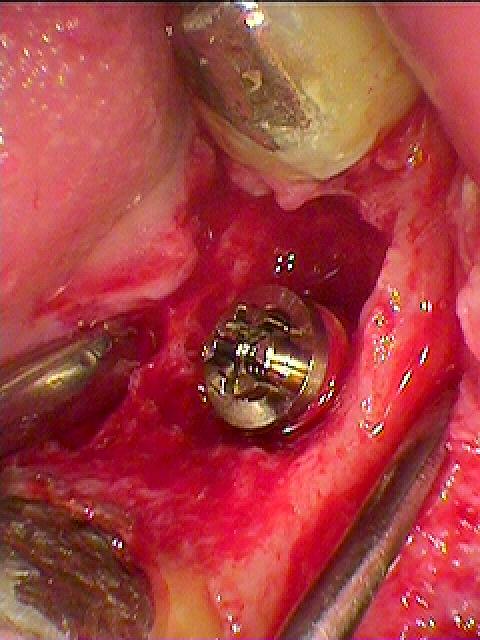

骨欠損が大きくGBRしていきます

下顎7番のインプラント埋入は下顎管とも近くなり、難しさはあります